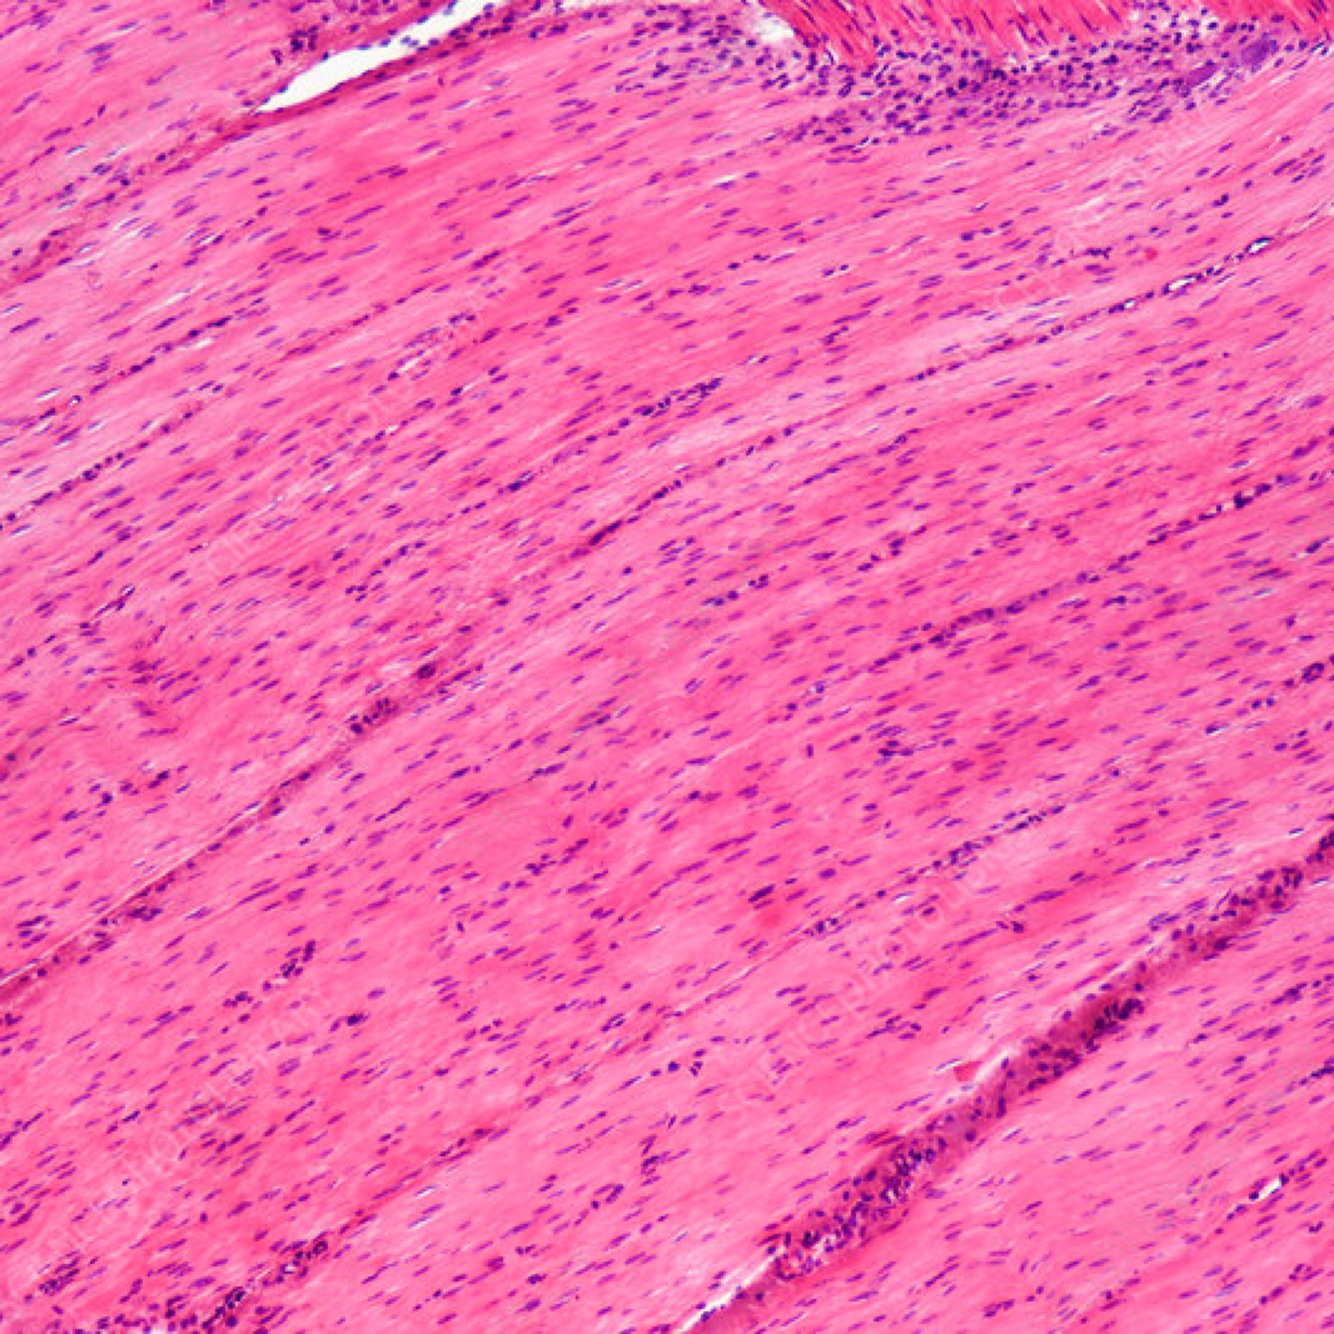

7

Q

ID the muscle tissue

A

Skeletal Muscle tissue